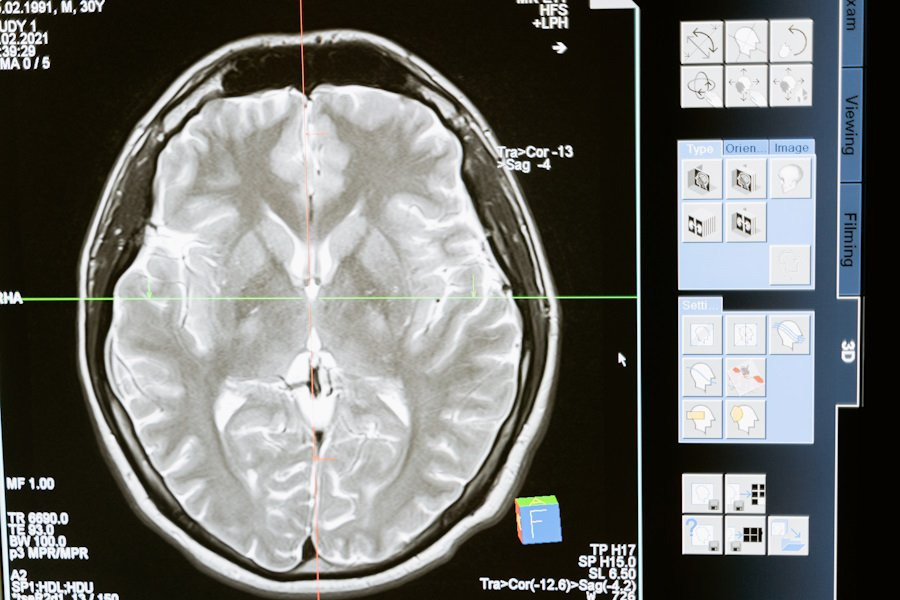

Фото из открытых источников

Исследователи из Kyushu University (Япония) сделали важный шаг в лечении рассеянного склероза (РС), серьезного заболевания, поражающего центральную нервную систему. В исследовании, опубликованном на портале Scientific Reports, команда выявила новую терапевтическую цель для лечения РС на поздних стадиях.